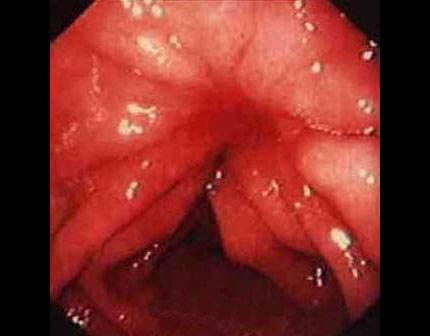

摘要:痔瘡癌變是嚴(yán)重的健康問題,其前兆包括便血、疼痛、肛門不適、排便習(xí)慣改變等10個(gè)跡象。了解并識(shí)別這些前兆的重要性在于早期發(fā)現(xiàn)、診斷和治療,以提高治愈率和生存率。對于痔瘡患者,密切觀察并及時(shí)就診是預(yù)防癌變的關(guān)鍵。

痔瘡是一種常見的肛腸疾病,雖然大多數(shù)情況下并不會(huì)引發(fā)癌變,但長期忽視可能導(dǎo)致病情惡化,了解痔瘡癌變的前兆,及早發(fā)現(xiàn)并采取相應(yīng)措施至關(guān)重要,本文將詳細(xì)介紹痔瘡癌變的10個(gè)前兆,以幫助讀者更好地預(yù)防和治療痔瘡。

痔瘡癌變是指痔瘡長期未得到有效治療,導(dǎo)致細(xì)胞異常增生,最終演變?yōu)榘┌Y的過程,其發(fā)生原因主要包括長期慢性炎癥刺激、不良生活習(xí)慣、遺傳因素等,了解這些原因有助于我們更好地預(yù)防痔瘡癌變。

痔瘡癌變的10個(gè)前兆

1、痔瘡疼痛加?。褐摊徎颊呷绺杏X疼痛逐漸加劇,可能是癌變的一個(gè)信號。

2、痔瘡出血:長期痔瘡出血,尤其是出現(xiàn)持續(xù)性出血時(shí),應(yīng)警惕癌變的可能。

3、痔瘡體積變化:如痔瘡體積在短時(shí)間內(nèi)迅速增大,可能是癌變的征兆。

4、排便習(xí)慣改變:如排便頻率增加或減少,以及出現(xiàn)便秘與腹瀉交替的情況,可能與痔瘡癌變有關(guān)。

5、肛門不適:出現(xiàn)肛門墜脹、異物感等癥狀時(shí),應(yīng)考慮痔瘡癌變的可能性。

6、消瘦和乏力:如體重迅速下降、乏力等全身癥狀出現(xiàn)時(shí),可能是痔瘡癌變的警示信號。

7、淋巴結(jié)腫大:如出現(xiàn)腹股溝或盆腔淋巴結(jié)腫大,可能與痔瘡癌變有關(guān)。

8、食欲減退:長期食欲減退,尤其是伴有上述癥狀時(shí),應(yīng)警惕痔瘡癌變。

9、肛周瘙癢:肛周瘙癢可能是痔瘡炎癥的表現(xiàn),長期不緩解可能發(fā)展為癌變。

10、便血顏色變化:如便血顏色由鮮紅色變?yōu)榘导t色或混合有黏液,應(yīng)引起重視。